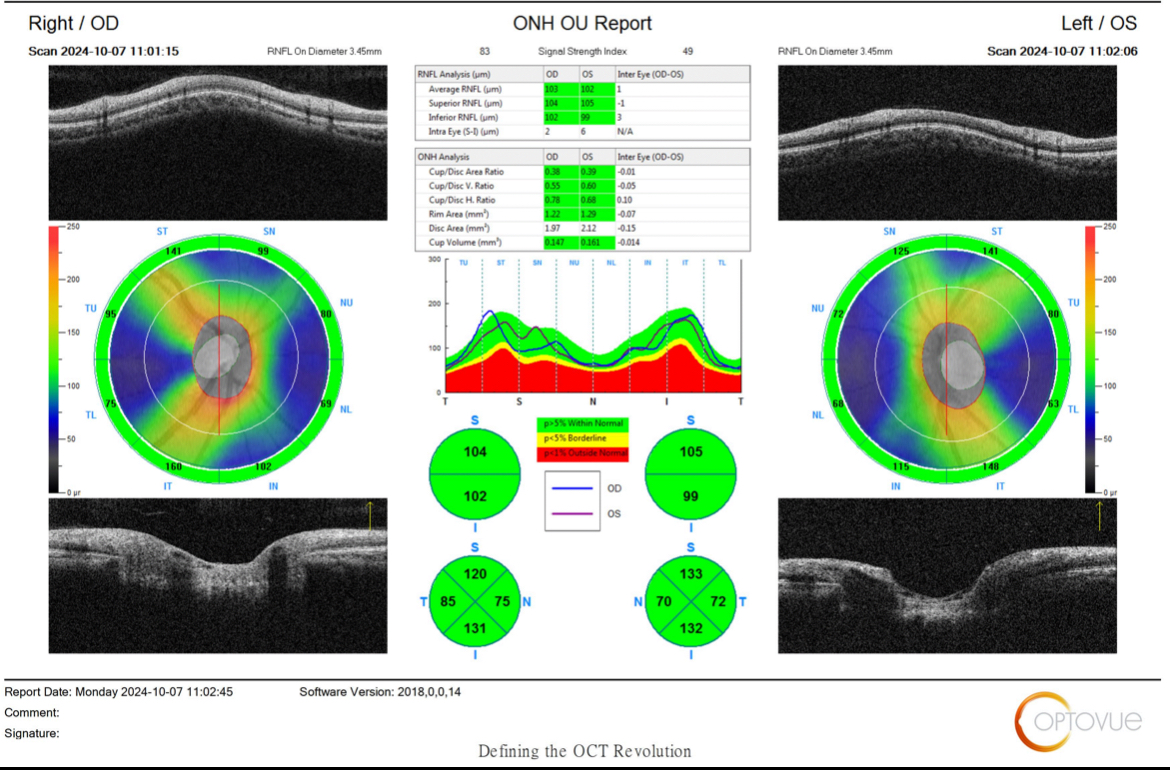

本人今年28歲,三年前健檢就有被標註左眼眼壓超標24,那時候沒有很在意,今年健檢又被測出右眼眼壓24,兩眼眼壓都偏高19~25左右

健檢中心請我要去醫院追蹤有可能是青光眼,目前去做了三總的OCT檢查,還要視野檢查等等還沒做,但是排到好久以後,心裡越想越害怕,

想請版主及各位幫忙看看我的OCT報告是否有青光眼?謝謝!

視神經厚度很正常很厚,但杯盤比較大,接近邊緣值,加上眼壓較高,所以目前看起來是疑似,未來可能是也可能不是,目前判斷不出來,所以要定期檢查,一年或半年去檢查一次就可以了

另外你視野一定正常,不用擔心